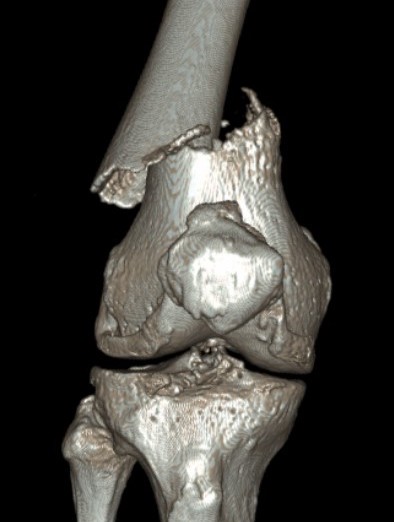

Type C: Complete articular

Xray / CT

Options

Dual plate

Indications

Significant comminution

Loss of medial cortical buttress